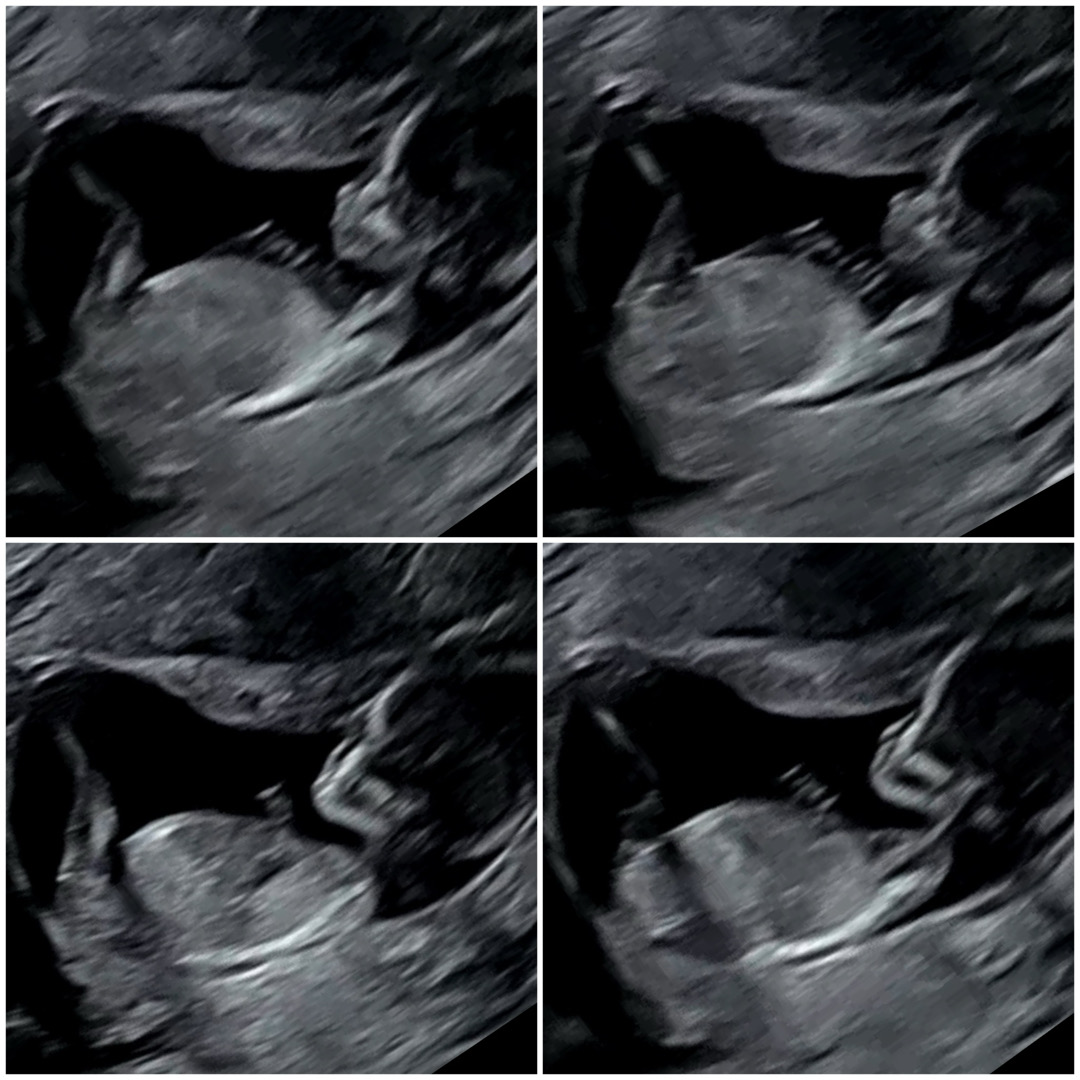

12주 각도법 고수님들🥰 지나가다 하나씩만 투표부탁드립니다~~~